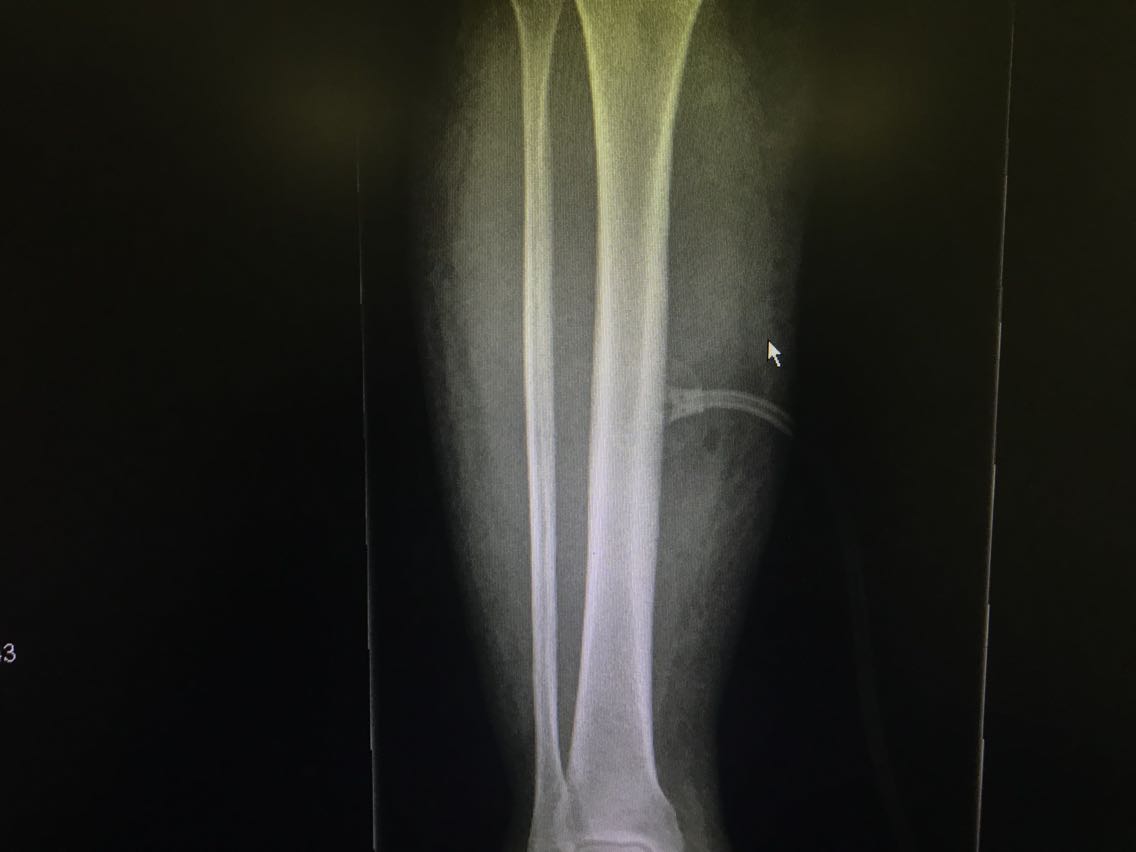

患者女性,54岁。 主诉:车祸伤致右下肢出血伴活动受限18小时。 现病史:18小时前患者乘坐摩托车时被汽车撞击发生车祸,致右下肢开放性损伤,皮肤软组织撕裂,创面出血。无意识障碍等不适。就诊于当地医院,查右下肢DR示:未见明显骨折征象。现为求进一步治疗,就诊于我院,急诊入我科。 既往史无特殊。

查体:右侧小腿中段后内侧见一大小约5*4cm创面,周围软组织肿胀。 辅助检查: 右下肢DR示:未见明显骨折征象。